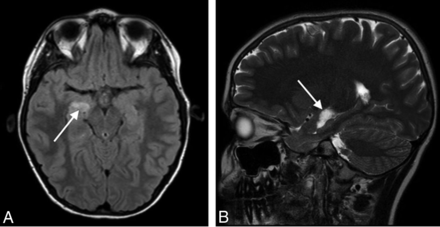

Six studies demonstrated abnormalities for which the differential diagnosis included neoplasm. There were 5 cases of presumed low-grade glioma and 1 of a suspected dysembryoblastic neuroepithelial tumor (Fig 3). Two of these did not have a follow-up study available, while the other 4 were unchanged on follow-up contrast MR imaging. In 2 studies performed for GHD, the suspected mass delayed growth hormone therapy until stability was confirmed on follow-up MR imaging. Two studies were performed for CPP, and the presence of a possible neoplasm did not prevent treatment. The findings in the 2 remaining cases also did not affect management decisions. The patient with suspected dysembryoplastic neuroepithelial tumor did not undergo follow-up imaging or subspecialty referral to neurosurgery due to family preference.

Axial FLAIR (A) and sagittal T2WI (B) show a hyperintense mass lesion (arrows) in the right mesial temporal lobe immediately superior to the hippocampus, most likely representing a low-grade neoplasm. Sagittal T2WI is helpful for localization of this lesion and differentiating it from the choroid plexus in the temporal horn. Although this finding was unrelated to the patient's presentation of GHD, intravenous contrast was needed for complete MR imaging assessment and showed the lesion to be nonenhancing (not shown).